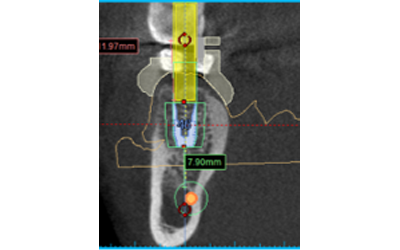

複雑な神経の治療は従来歯科医師の熟練度や勘に頼って行っていたものが、【見て治療する】ことにより、予知性の高い治療を提供できます。

初回:他院で治療するも痛みが取れず、中を確認すると、神経の穴は1つのようですが…

丁寧に中を確認すると、実はもう1つ神経がありました。これは、拡大しないと見つけられません!

初回終了時です。これで問題がなければ、次回で根の治療は終了です!

立体的な歯や骨を従来のレントゲンとは異なり、三次元で確認できることにより、従来のレントゲンではよくわからなかった病変部や骨の状態を調べることにより正確な診断を行うことが出来ます。